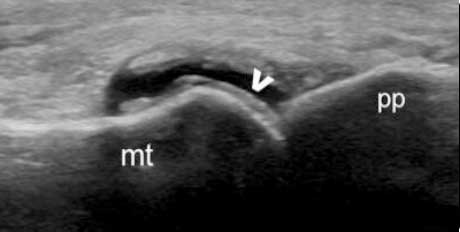

二、清晰显示软骨表面尿酸盐结晶沉积状况 判断痛风所属病期

肌骨超声可通过高清影像图判定软骨表面有无出现一条与强回声骨皮质平行的线样强回声,即“双轨征”这一痛风性关节炎特征性表现,判定疾病所属。当尿酸盐粘附并沉积于漂浮的滑膜上时,超声检查可在关节腔内发现漂浮的高亮回声;而当尿酸盐长期沉积于韧带上时,在超声中即显示条带状的略高回声(韧带)中出现高回声点、高回声带或高回声团块(尿酸盐),从而判断痛风病情处于哪一时期。

“双轨征”

跖趾关节软骨表面可见高回声不规则增强的软骨滑膜边缘线,呈“双轨征”。

高回声带

软骨表面回声增强,与深面的骨性关节面强回声线形成“双轨征”。